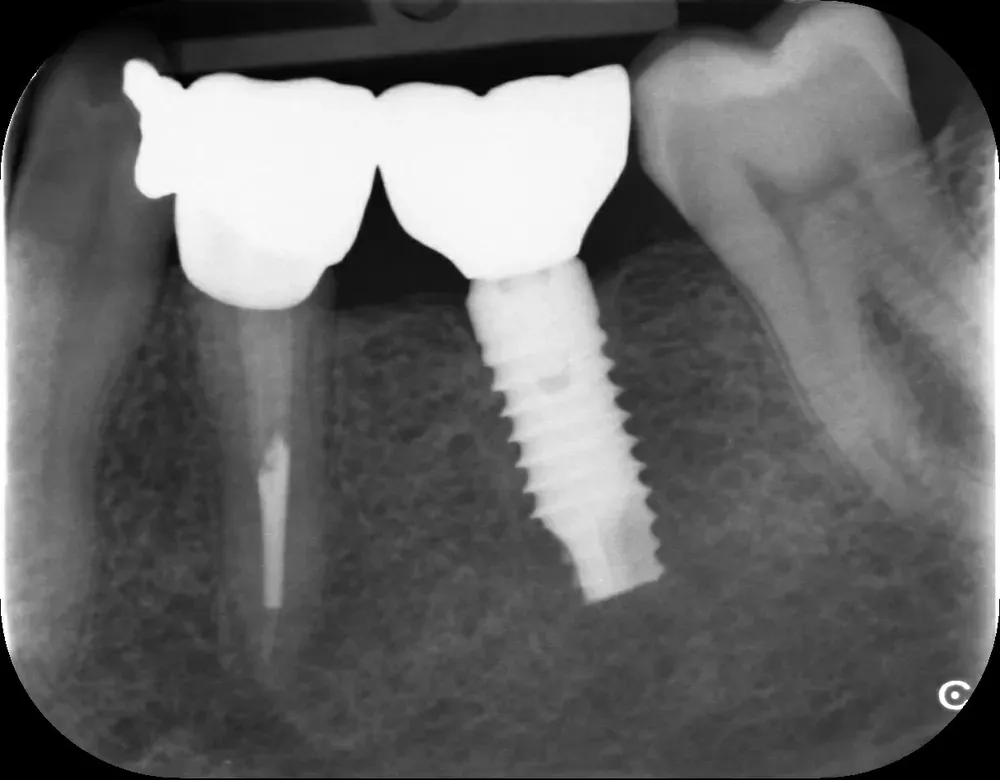

Gli impianti transmucosi devono essere posizionati transmucosi, soprattutto se hanno connessioni non particolarmente “sigillanti”. Usati in tal guisa, sono perfetti. Le immagini che seguono dimostrano che i transmucosi, se posizionati al giusto livello verticale, causano ZERO riassorbimento della cresta ossea.

Per concludere il confronto tra le varie connessioni, l’immagine che segue è una radiografia con due impianti affiancati: un tissue-level ben posizionato fatto da un collega anni addietro e un impianto a connessione conica in posizione infracrestale con abutment della corretta lunghezza per il caso. Il secondo è un mio caso. È interessante notare come il cono dello spazio biologico sia identico. Se ben posizionati, tutti gli impianti funzionano egregiamente (l’impianto più vecchio inizia a soffrire un pochino, ma questa è un’altra storia).